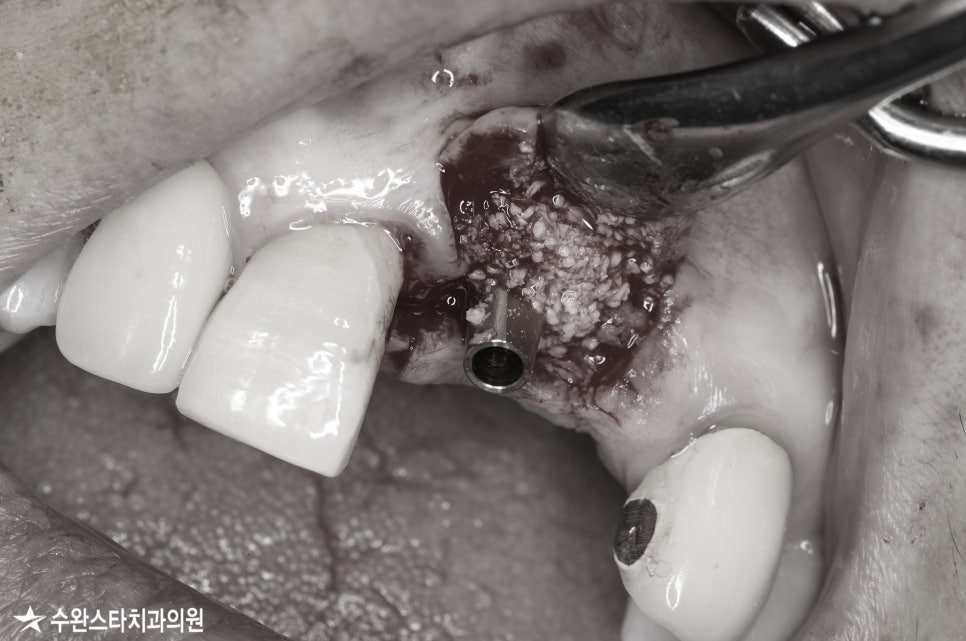

뼈이식 모습, 50대 여성 (2022.09)

어버트먼트 사이로 빈 공간에

뼈 이식을 동반하여 부족한 골량을

채워주는 모습입니다.